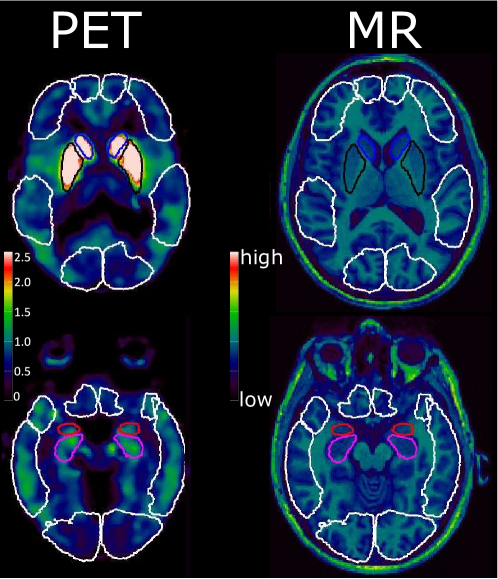

Understanding brain mechanisms is essential to improve prevention and treatment of brain disorders. For instance, it has been hypothesized that the serotonin system is a key factor in major depressive disorders (MDD) and most antidepressants attempt to act on this system. Unfortunately, less than half of the patients respond to first-line antidepressant treatment. A deeper understanding of the serotonin brain system is therefore needed. While it is not yet possible to non-invasively measure the extracellular level of serotonin in the brain, medical imaging allows one to simultaneously visualize the brain structure (using Magnetic Resonance Imaging - MRI) and quantify the binding potential of certain serotonin receptors (using Positron Emission Tomography - PET), e.g. see Figure 1.